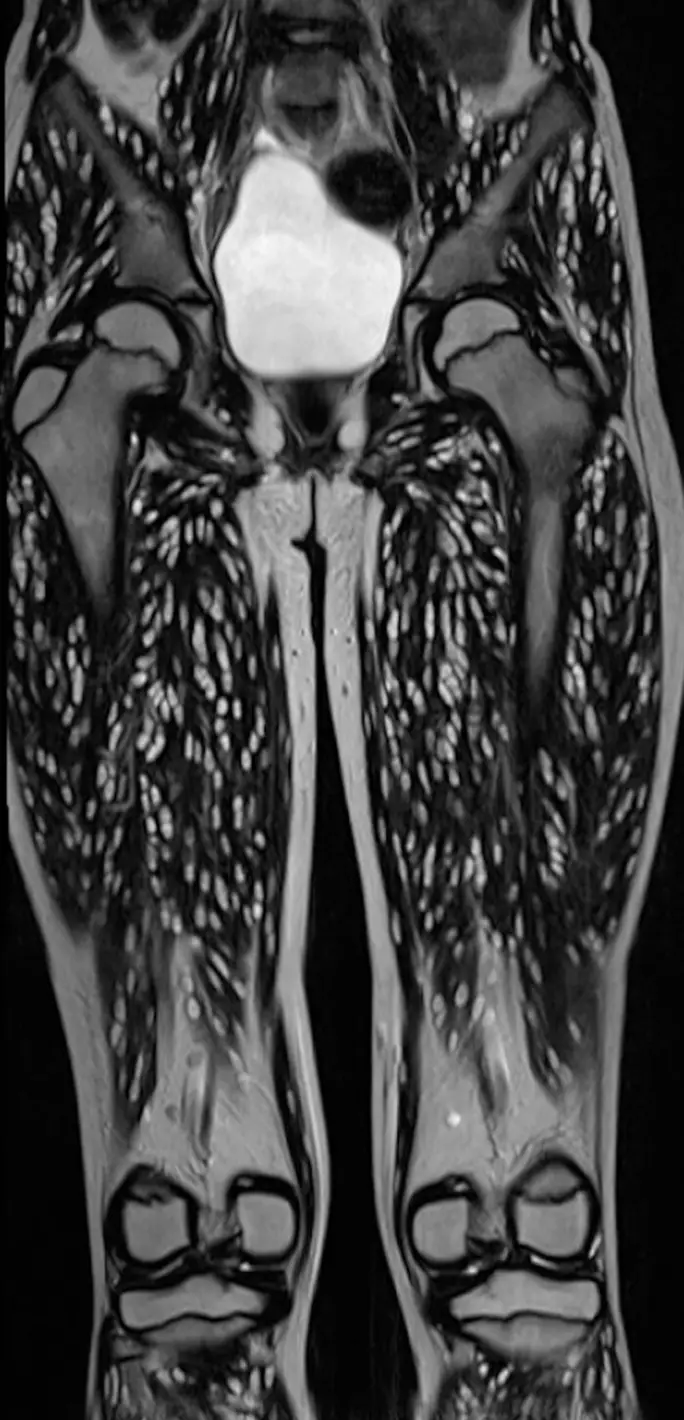

Published by medical professionals Mohd Ilyas and Vikrant Mahajan, the pair shared CT scans of the young girl’s legs and brain.

The CT scans show that, as a result of eating the undercooked meat, the girl’s brain and legs were full of parasites, leading E.R. Doctor Sam Ghali M.D. to post them to X (formerly known as Twitter), calling them ‘one of the craziest CT scans [he’s] ever seen’.

Another comment was confused by what they were looking at outside of the fact it was bad, to which another replied: “Yes. Every single shred of muscle visible on that scan is infested. It’s shocking.”